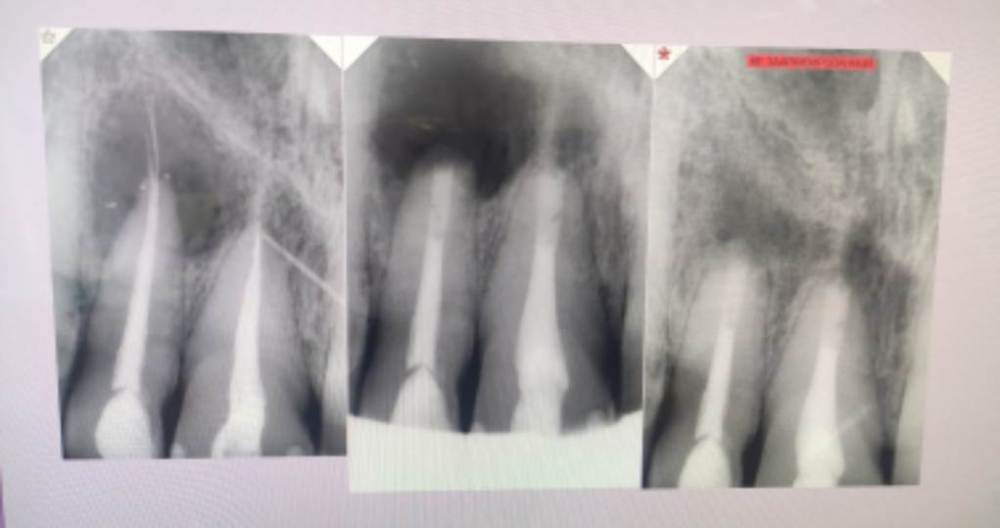

Алияfest Опубликовано 15 июля, 2023 Поделиться Опубликовано 15 июля, 2023 Всем привет ну ,лично я часто встречаю такие периодонтиты из последнего случая ,зуб 11 выведена гуттаперча ,пациент направлен ко мне ,разбитый апекс под микроскопом я извлекла гуттаперчу из-за апекса ,остатки силера немного есть ,очаг за три года по кт увеличился с 5 и 5 до 7 и 7 ,сейчас обострение ,пациентка на на ГВ ,отказывается пить антибиотики случай в рамках одной клиники Устраиваю переговоры с пациенткой и необходимости приема начальство в отказ удалять зуб несмотря на то что пациентка уже сама не против ,так как зуб болит по стенке у апекса осталось немного гутты,в прошлый раз полезла ,после предыдущего доктора ,и был сильный кровоотток,ничего не было видно ,еле остановила и оставила кальций (без примесей ),так как работали около двух часов Ломаю голову чем достать эту гутту пристеночную ,глаза были сломаны ,но не мой дух чувствую полное одиночество и уже жалею ,что решила помочь пациентке и клинике ? Ссылка на комментарий